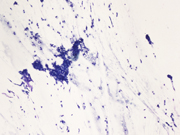

Figure 1: Rapid on-site evaluation (ROSE) FNA material of the left upper arm lesion, smear, Diff-Quik stain, 100x magnification.

Figure 2: Rapid on-site evaluation (ROSE) FNA material of the left upper arm lesion, smear, Diff-Quik stain, 200x magnification.

The smears (Figures 1-4) show a cellular lesion composed of uniform round-to-oval cells in tight and loose cohesive clusters admixed with strands of magenta-colored material reminiscent of basement membrane. Spindled endothelial cells might be imagined in the periphery or crossing the cell clusters. The cell block material (Figure 5) shows uniformly rounded cells with punched-out nuclei, evenly dispersed nuclear chromatin with inconspicuous nucleoli, and eosinophilic cytoplasm growing around blood vessels. Immunohistochemistry performed on the cell block materials shows that the cells of interest are diffusely positive for SMA (Figure 6), while negative for AE1/3, synaptophysin, chromogranin, S100, and CD31. Ki-67 is very low. The cytologic findings are classic for glomus tumor (GT).